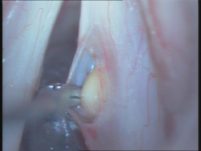

ניתוח ציסטה צעד 1:

ניתוח ציסטה צעד 2: